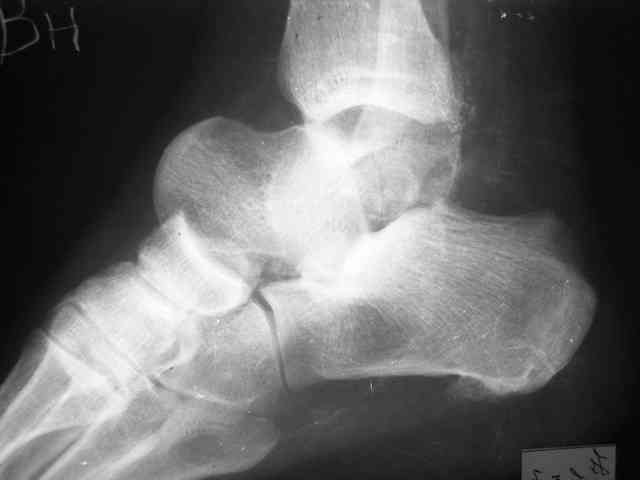

Уважаемый Александр! Как обещал представляю Р-граммы и операционные фото.

Последний снимок

Мнение по поводу тарана? АН есть?

> Мнение по поводу тарана? АН есть?

Типичная картина некроза.